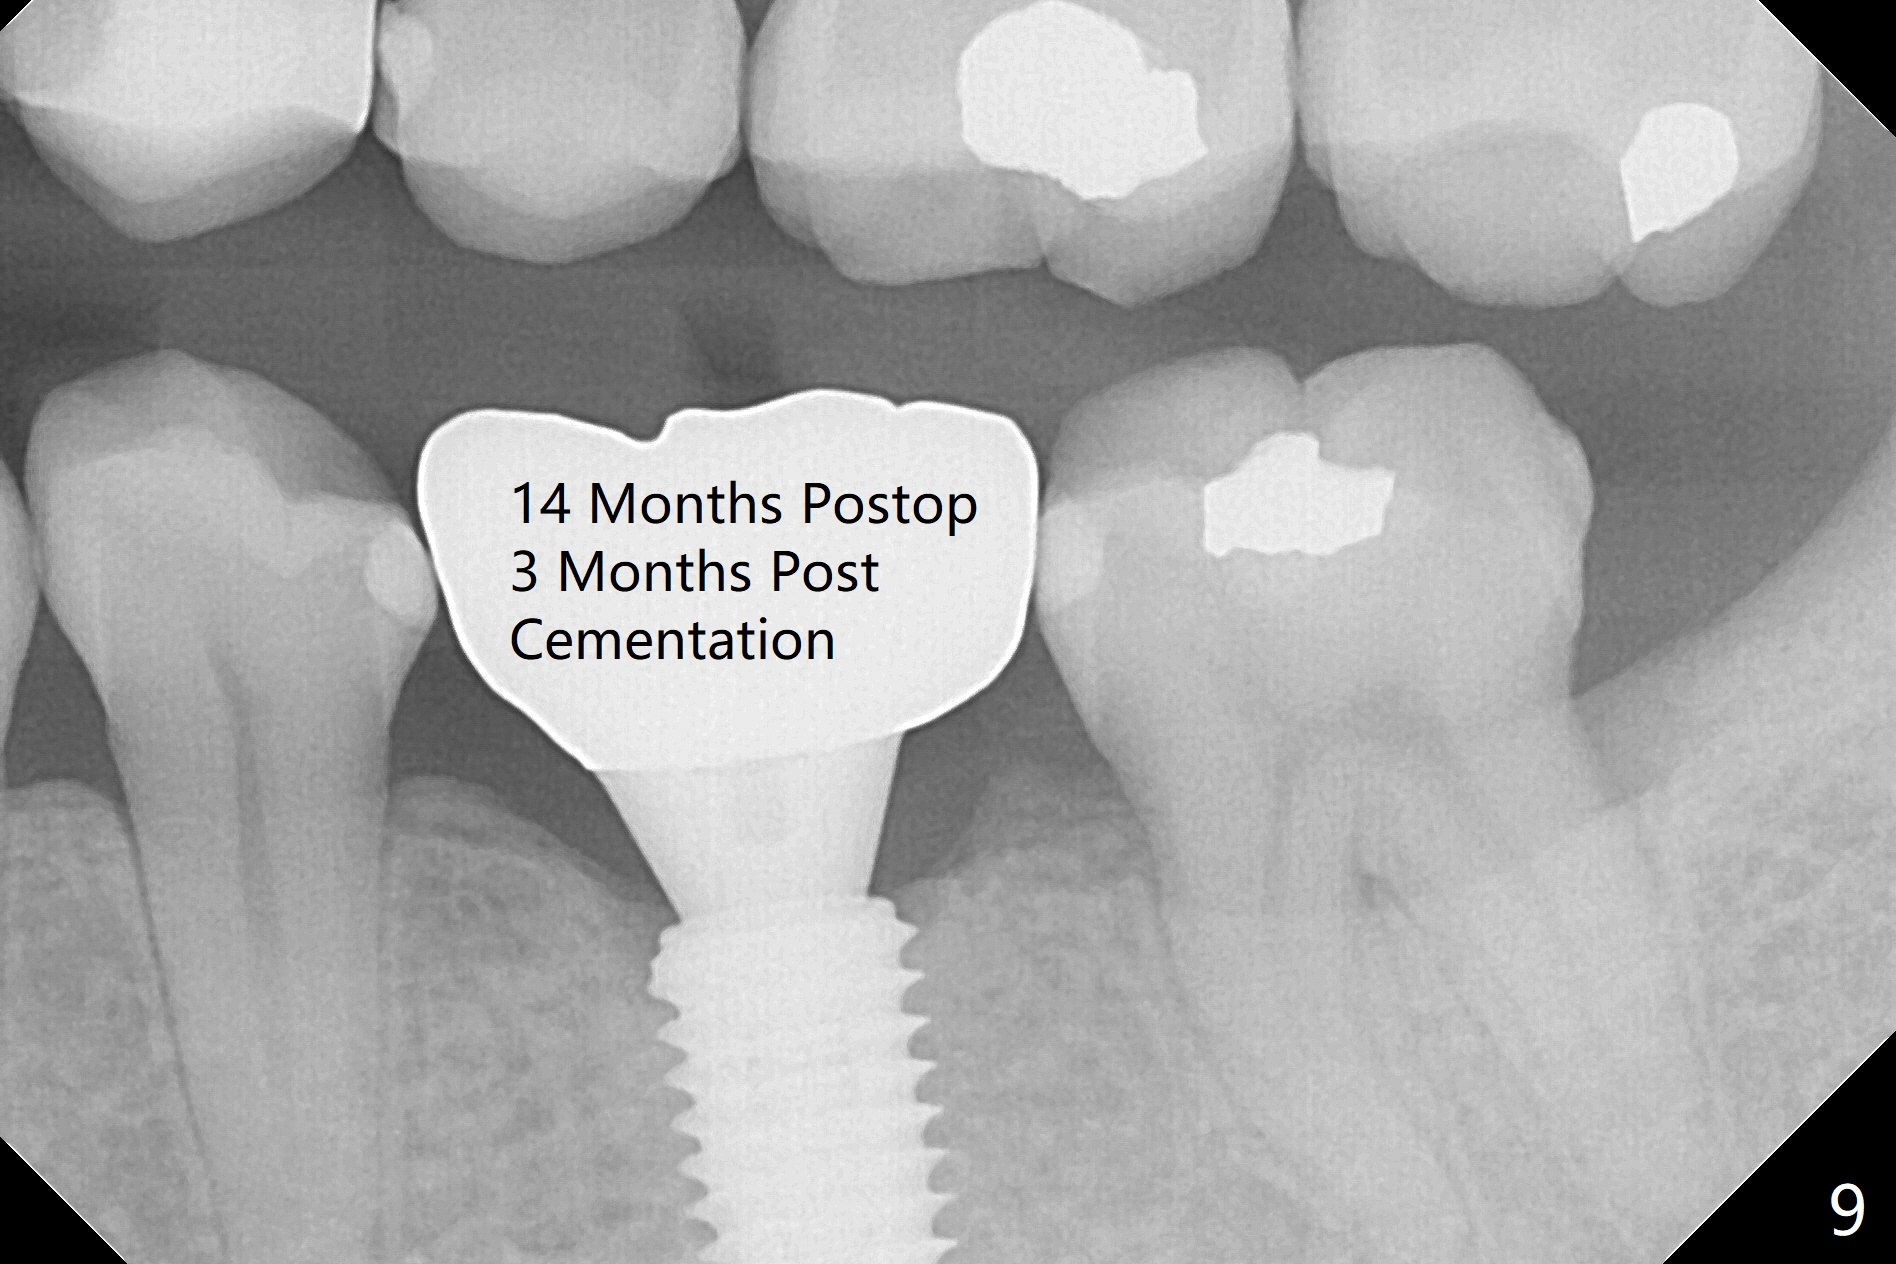

A 5x10 mm implant is intentionally placed distal at #19 using guided surgery (Fig.1). When it is osteointegrated, it will be used as an anchorage to upright the tooth #18 orthodontically. In fact the implant is mistakenly placed 1.5 mm deeper than planned without significant side effect (red dashed line: the superior border of the Inferior Alveolar Canal). The tooth #17 will be extracted before banding. The healing abutment dislodges (probably as related to deep placement of the implant) 20 days postop and is retightened. There is mild crestal bone loss 4 months postop (Fig.2). The tooth #17 is extracted with insertion of Osteogen Plug to prevent dry socket. A 5x4(2) mm cementation abutment will be placed with fabrication of a provisional with equi- or slightly subocclusal. Bands and brackets will be placed at #18-22. When open coil spring is placed between #18 and 19 with 18 ss wire, acrylic will be added to the occlusal surface of the provisional so that the tooth #18 is distalized without interference. The tooth #18 is distalized more than 1 month post placement of open coil spring (Fig.3). The tooth #18 is also lingually tilted (Fig.5), as compared to the contralateral side (Fig.4). After placement of 20 ss wire and longer coil spring, an elastic is placed between the lingual cleat of #18 and the buccal (lingual) button of #15 (Fig.5) to correct the lingual tilt. The tooth #18 is distalized ~ 1 mm shown by X-ray, although more clinically, 2.5 months post open coil spring (Fig.6). The bone density around the implant, particularly mesial, increases, as compared to Fig.2. The treatment finishes with normal overjet in the 2nd molars 11 months postop and 5 months post banding (Fig.7). It appears that the buccal groove of the lower 2nd molar (Fig.8 >) has been distalized to occlude with the mesiobuccal cusp of the upper 2nd molar (^). The width of the dense bone around the implant increases 14 months postop (3 months post cementation, Fig.9).